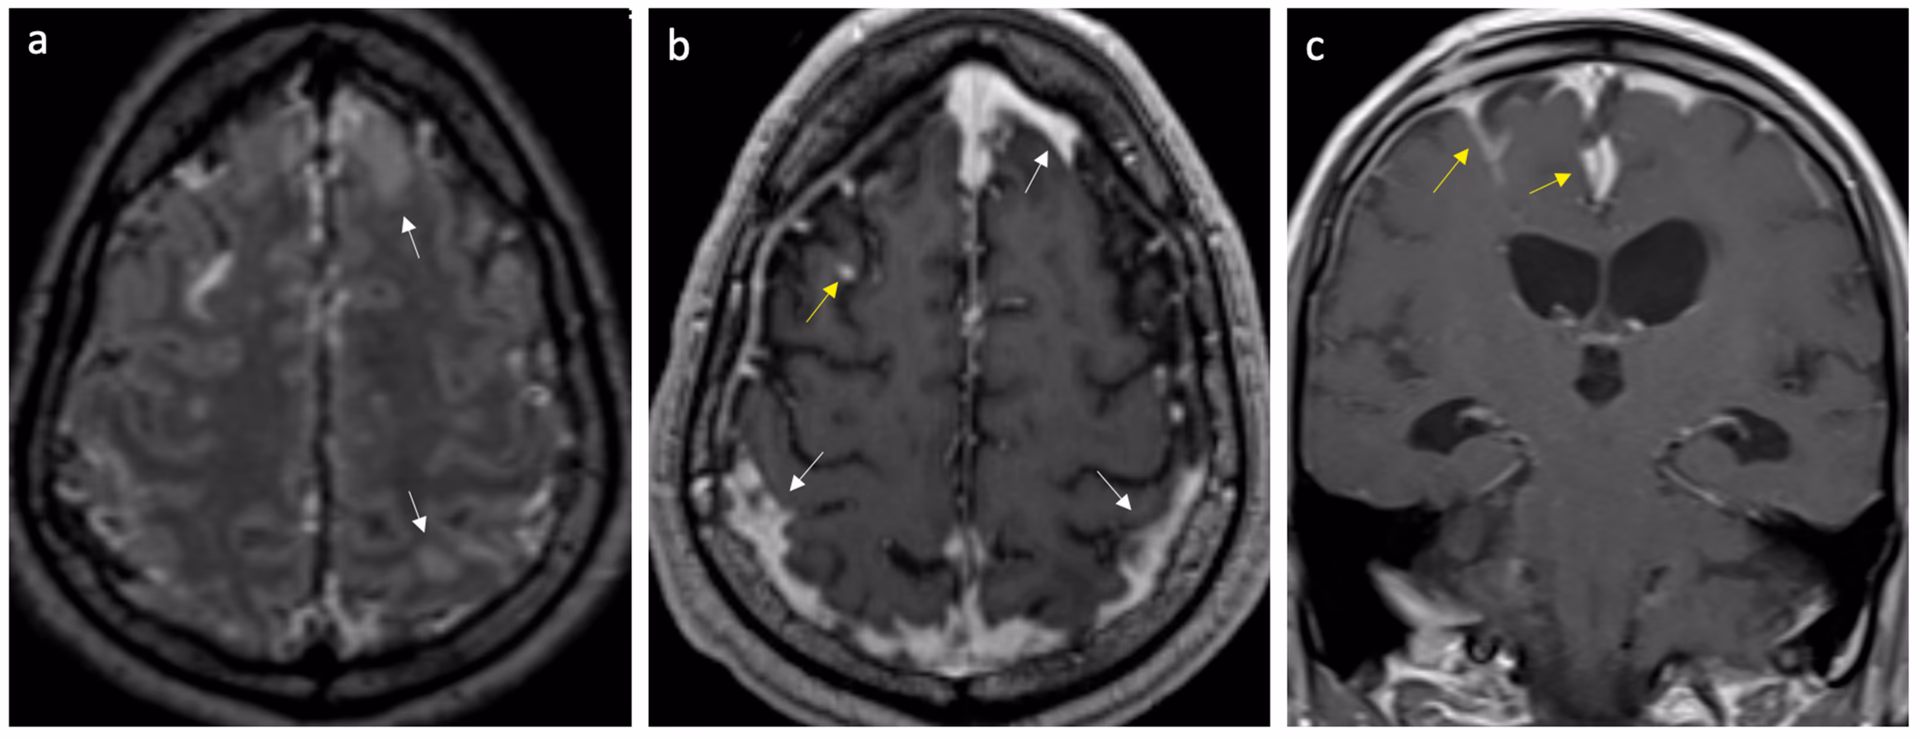

- Billeddiagnostik: En CT- eller MR-scanning af hjernen kan udføres for at udelukke andre årsager til symptomerne, såsom en hjerneblødning.